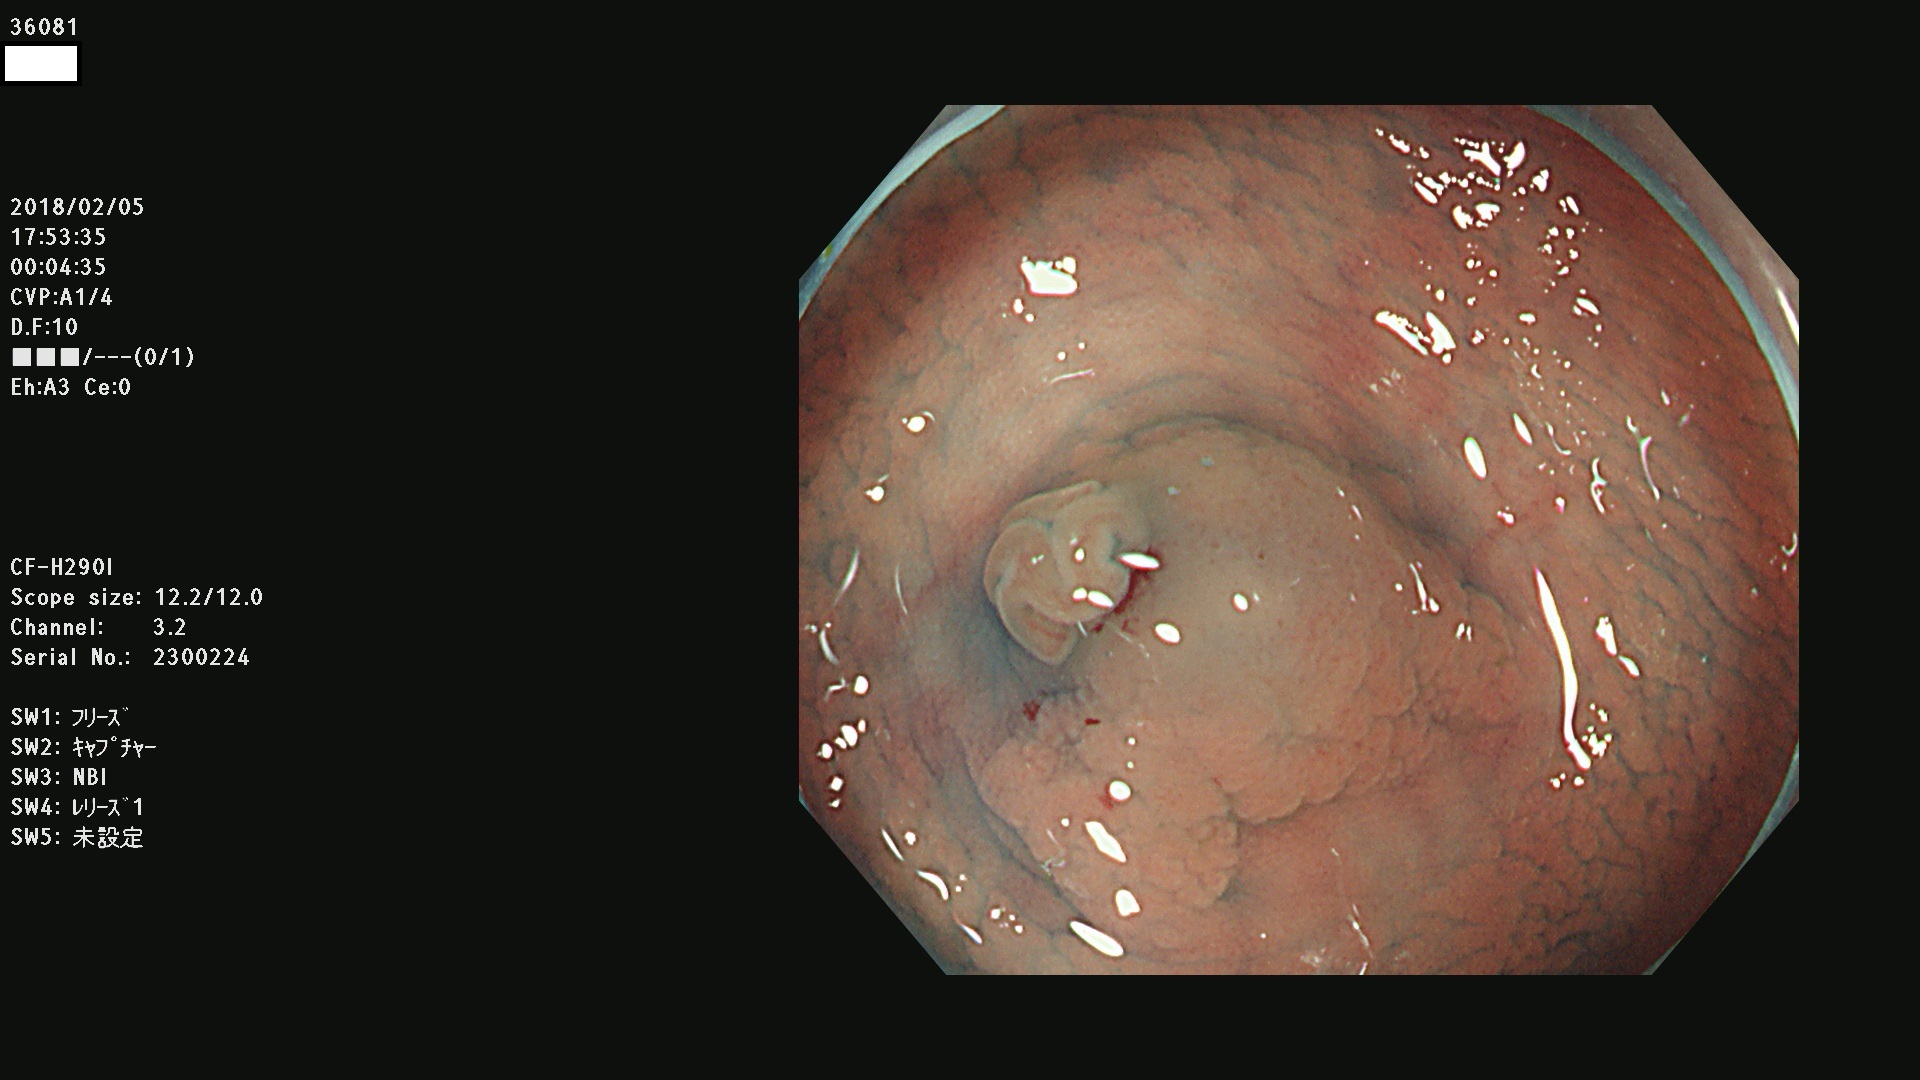

36000 36001 36003 36004 36008 36009 36012 36013(SSA/Pのみ) 36015 36016 36017 36021 36022 36023 36027 36030 36033(SSA/Pのみ) 36036 36037 36042 36044 36045 36046 36047 36051 36053 36054 36055 36056 36057 36058 36059 36060 36061 36062 36073(SSA/Pのみ) 36074 36075 36076 36078 36081 36082 36083 36089 36090(SSA/Pのみ) 36094 36096

発見困難で危険性の高い平坦型病変(上記100名より抽出)